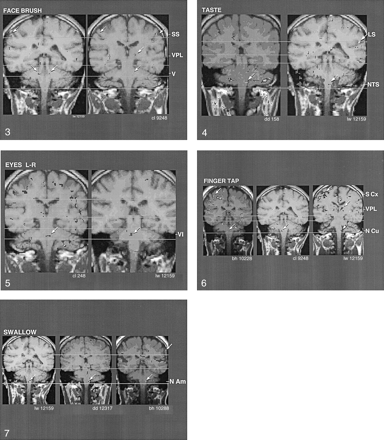

As shown in Figure 3, consistency was observed between the regions of BOLD activation in the pons and somatosensory cortex in two individuals, in response to brushing of the face. In addition, note the region of BOLD activation in the somatosensory thalamus (ie, VPL) in one of the individuals (right image). The triple activation in response to brushing the face was consistent with facial stimulation–induced activation of main trigeminal nucleus of the pons (CN V), VPL of the thalamus, and homuncular facial region of the somatosensory cortex. A probable clinical correlate of these findings of a response to face brushing is the report of cutaneous anesthesia in the maxilla and other facial regions in two cases of a relatively circumscribed lesion in this brain region (26). For bilaterally activated motor or sensory tasks, we often observed only unilateral BOLD activation; this finding was consistent with that of previous reports (19, 20).

Coronal images show the similarity of activation (arrows) produced by brushing the face, which corresponds to the region of the trigeminal main sensory nucleus (V), in two individuals. Note activation of nucleus ventralis posteromedialis (VPL) in one of the individuals and of somatosensory cortex (SS) in both individuals.

Figure 4 shows interindividual consistency in BOLD activation in the region of the superior level of the NTS in the medulla oblongata, in correlation with the taste stimulus. Note the activation of the sensory cortex (right image) at the level of the lateral sulcus, which closely corresponded to the homuncular tongue region.

Figure 5 shows interindividual reliability in the region of BOLD activation in correlation with left-to-right eye movement. The pontine location of activation near the midline was consistent with activation of the abducens nucleus (CN VI). Figure 6 shows that the region of BOLD activation in relation to finger tapping was consistent among three individuals. This finding corresponded to the region of the nucleus cuneatus, which receives afferent activity from the hands. In addition, the region of BOLD activation in the sensory cortex corresponded to the homuncular region for the fingers (note that this region of activation was superior to that in the face in Figure 2). Furthermore, in one subject (right image), BOLD activation was evident in the somatosensory thalamus (region of the nucleus VPL); this finding was consistent with afferent activation from the fingers.

Figure 7 shows the BOLD activation pattern that was correlated with dry swallowing (ie, Mendelsohn maneuver). This movement required activation of the nucleus ambiguus of the medulla oblongata. The images show that the region of the nucleus ambiguus was consistently activated in three individuals during the performance of this task. Note the activation at the inferolateral aspect of the motor cortex just superior to the lateral sulcus (upper arrow, right image), which corresponded to the homuncular pharyngeal region.